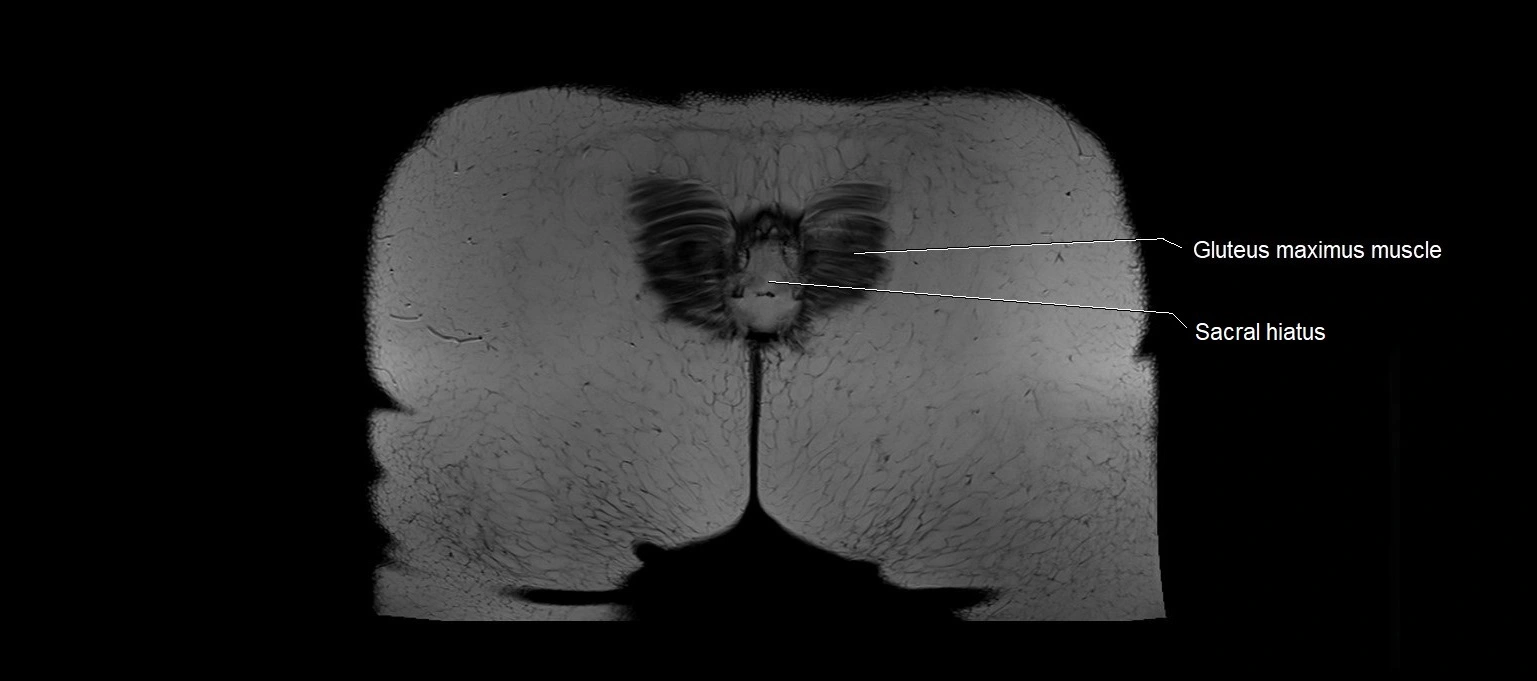

MRI images